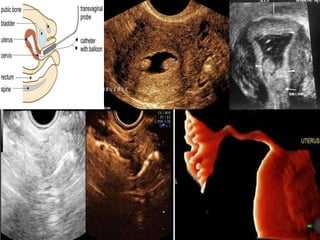

Hystero salpingogram (HSG)

STEPS

1 • Minimal Stimulation of ovaries

2 • Follicular Study +/- doppler studies

3 • Trigger with HCG / GnRha

4 • IUI – husband / Donor after 36 - 40 hrs

5 • Progesterone LPS

6 • UPT / B-hcg after 14 days